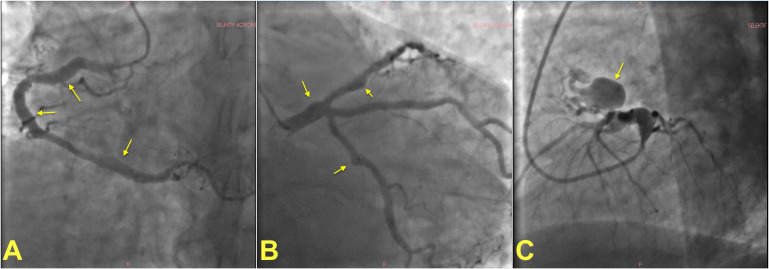

冠状动脉动脉瘤(CAAs)是常见的实体,高达8%的患者接受冠状动脉造影。CAAs最常见的病因是冠状动脉粥样硬化性“正性重塑”,同时先天性、炎症性和创伤性病因也可见。动脉瘤是血栓形成的中心,血栓可能阻塞动脉瘤段或远端栓塞。动脉瘤破裂是CAA的一种罕见但潜在的灾难性并发症。大多数动脉瘤可以通过药物治疗,而对于易于破裂或血栓形成的CAAs,经皮排除冠状动脉循环动脉瘤是合适的。手术矫正仍然是患者的最终选择谁不适合经皮管理或那些有令人信服的手术指征。本文综述了CAAs的命名、分类、病理生理学、诊断和管理方面的现有知识,并特别强调了减轻CAAs相关风险的治疗策略。

Coronary artery aneurysms (CAAs) are frequent entities that are encountered in up to 8% of patients undergoing coronary imaging. The most frequent cause of CAAs is atherosclerotic "positive remodeling" of coronary arteries, while congenital, inflammatory, and traumatic etiologies could also be seen. Aneurysms serve as foci for thrombus formation, which may occlude the aneurysmatic segment or embolize distally. Rupture of an aneurysm is a rare yet potentially catastrophic complication of a CAA. Most aneurysms can be managed medically, while percutaneous exclusion of an aneurysm from coronary circulation is appropriate for CAAs that are prone to rupture or thrombosis. Surgical correction remains the ultimate option for patients who are not amenable to percutaneous management or those with a compelling indication for surgery. This review summarizes the available knowledge on the nomenclature, classification, pathophysiology, diagnosis, and management of CAAs, with a particular emphasis on treatment strategies to mitigate the risks associated with CAAs.